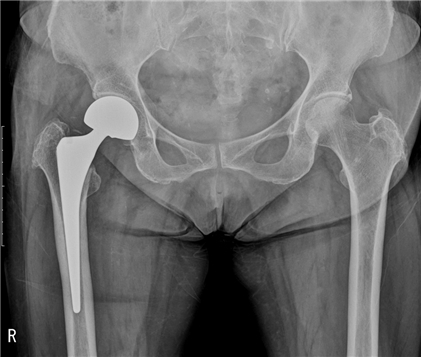

퇴행성 고관절염 초기에는 소염 진통제, 연골 보호제 등 약물 치료와 휴식, 적당한 운동을 병행하며 경과를 살피고 치료를 해야 해요. 고관절 통증 증상이 완화되지 않다면 관절 수술을 해야 해요.

고관절 통증 치료법

고관절 통증 증상의 진단과 치료 플랜은 통증부위를 중심으로 한 검사부터 시작돼요. 골반과 엉덩이 허리 등의 X-ray 촬영을 진행 골반이 틀어져 있지는 않은지 내부 구조적으로 불균형이나 문제 사항은 없는 지 등을 확인해요.

이어서 환자가 느끼는 통증의 정도를 평가한 뒤 이학적 검사로 고관절의 회전 정도 등을 파악해요. 더불어 필요한 경우에는 초음파검사, CT나 MRI 검사를 진행할 수도 있어요. 이후 수술이 필요한 심각한 상황이 아니라면 비수술적 요법인 프롤로 주사 등이 주로 진행돼요.